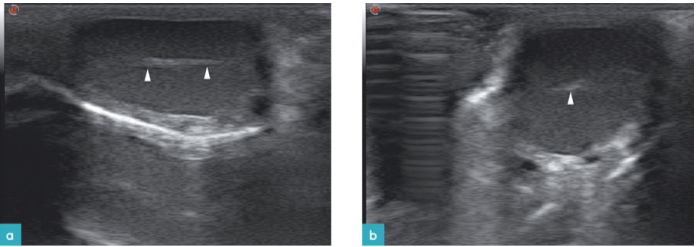

公猫生殖系统的超声扫查不如公犬的扫查常见,其数据图像较为少见,难以建立正常标准数据库。睾丸的回声细致均匀,睾丸白膜为一高回声薄的边界样结构。睾丸纵膈在矢状面上为中心高回声亮线,在横截面上为中心高回声亮点(图2)。

猫附睾的回声略低于睾丸的回声,且质地更为致密。猫的附睾体积明显小于犬的附睾体积,因此在超声上也较难看到。